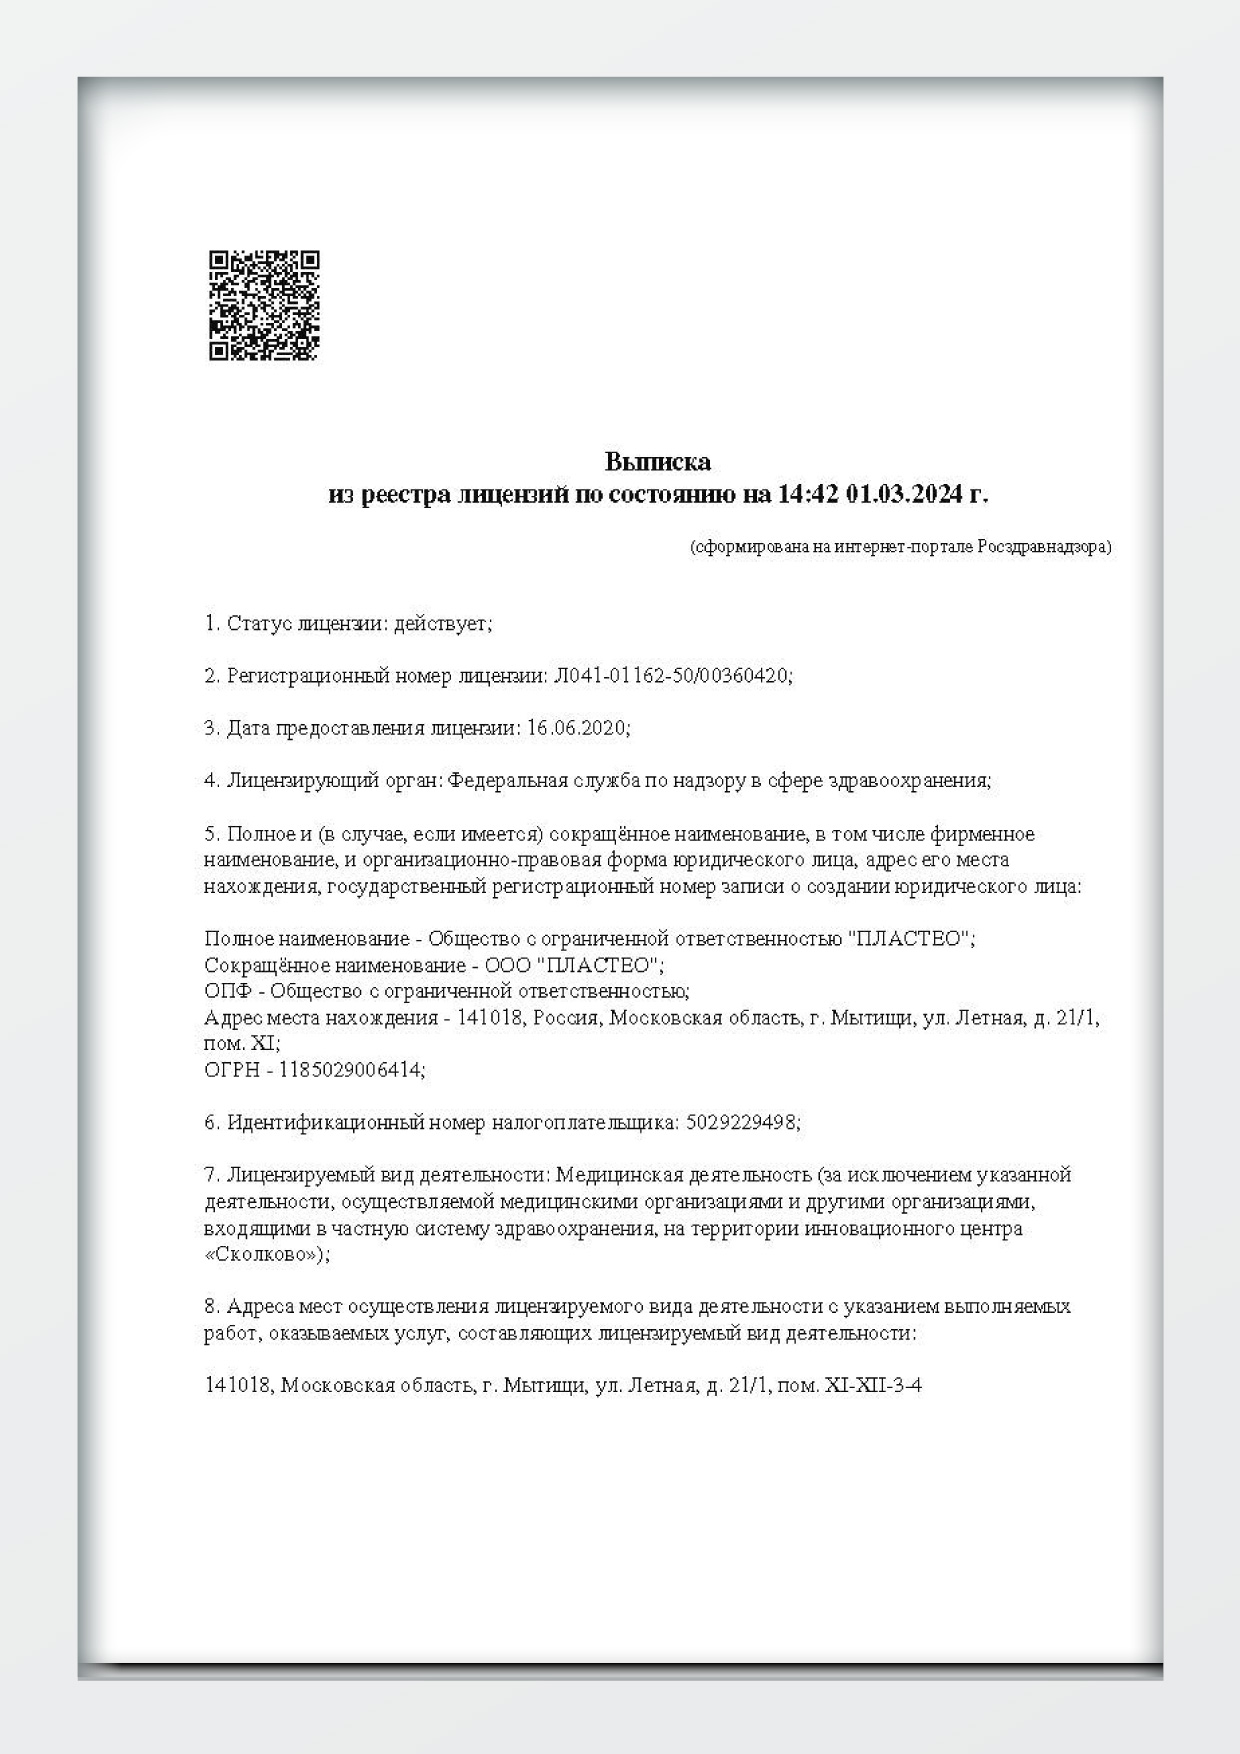

Наши лицензии